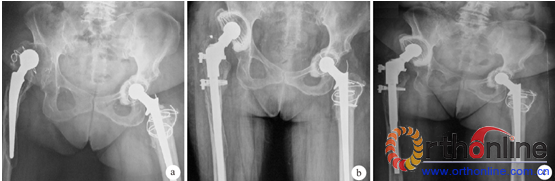

本组术后切口均Ⅰ期愈合,无下肢深静脉血栓及神经损伤等并发症发生。21 例均获随访,随访时间2 ~ 6 年,平均4.3 年。X 线片检查示,术中股骨干劈裂骨折于术后3 ~ 6 个月愈合。术后3 例活动时偶有大腿痛,服用非甾体类抗炎药物后缓解。术前髋关节周围感染者术后无感染复发,余患者均未发生感染。随访期间无假体松动,假体周围可见骨长入(图1)。末次随访时2 例出现股骨假体下沉,下沉< 5 mm,为非进行性下沉,无明显髋关节疼痛等症状,未作特殊处理。末次随访时Harris 评分为(82.7 ± 3.3)分,VAS 评分为(0.19 ±0.51)分,与术前比较差异均有统计学意义(P < 0.05)。

图 1 患者,女,62 岁,右侧人工全髋关节置换术后18 年出现右髋关节严重疼痛,活动受限,行右侧髋关节翻修术X 线片。 a 为术前,b为术后即刻,c为术后3 年